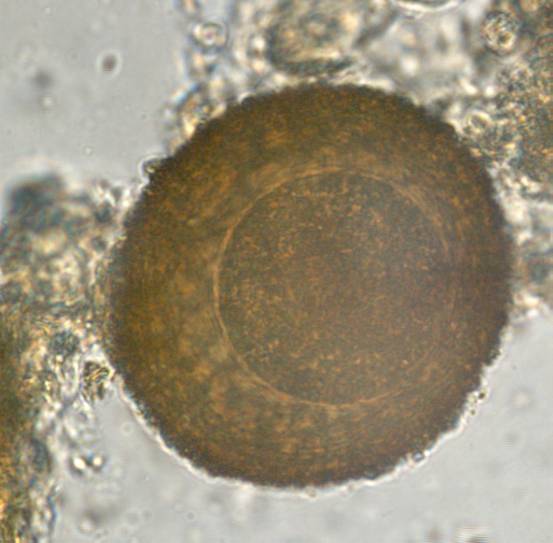

Coproscopy

All

Nematodes

Protozoa

Trematodes

Cestodes